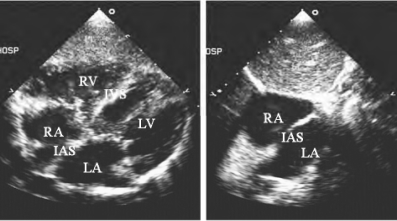

-